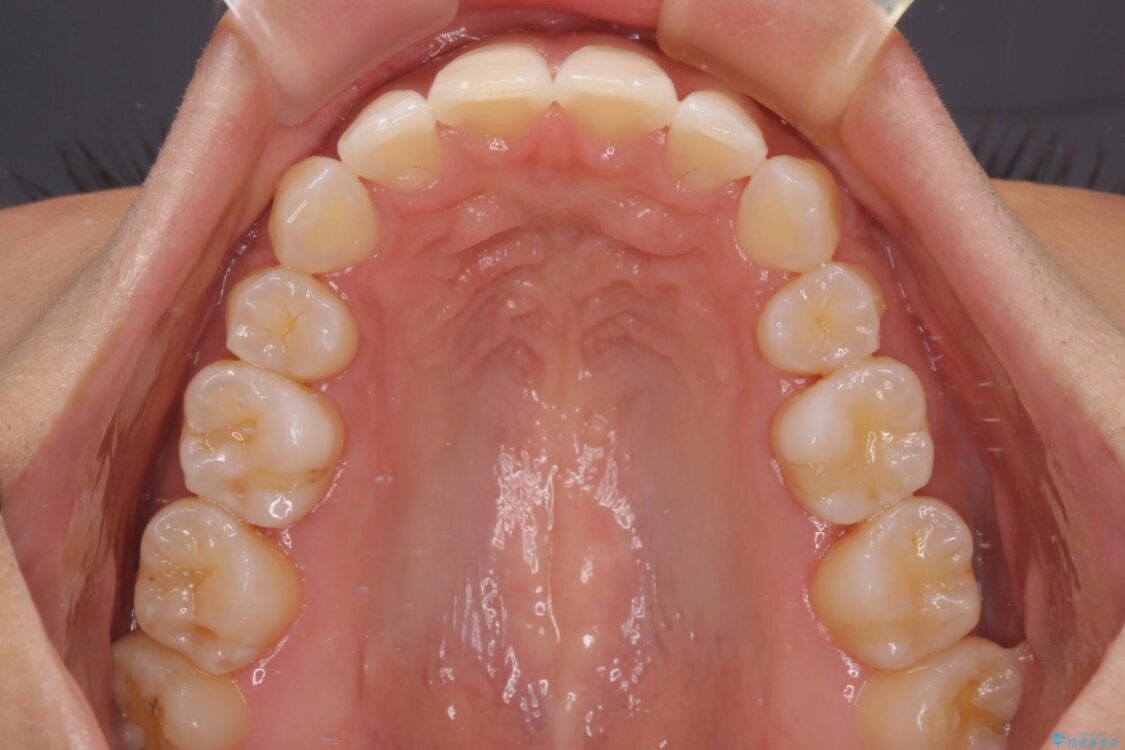

治療前

• 抜歯矯正で唇を閉じやすく 目立たないワイヤー装置 治療前画像